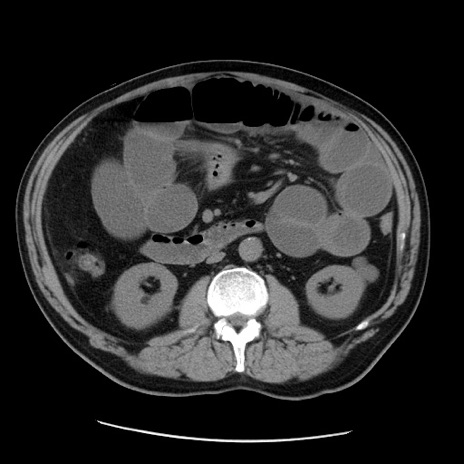

症例20(横断像)

【症例】 60歳代男性

【主訴】 腹部膨満、嘔吐

【現病歴】5日前頃より倦怠感を認め食事量減少し4日前の朝嘔吐、食事摂取困難となった。 3日前近医受診し点滴施行され整腸剤などを処方された。 当日他院を受診し、腹部膨満著明、炎症反応の上昇(CRP10.8、WBC11200)あり、紹介受診となる。

【身体所見】 意識JCS1 受け答えがはっきりしないBP 111/57mHg、 P 67bpm、、BT35.2°C、SpO2 97%(RA)、 腹部:膨隆、打診で鼓音あり、全体的に圧痛有り、腸蠕動音(-)、反跳痛ははっきりせず。

【データ】WBC 11400、CRP 14.20